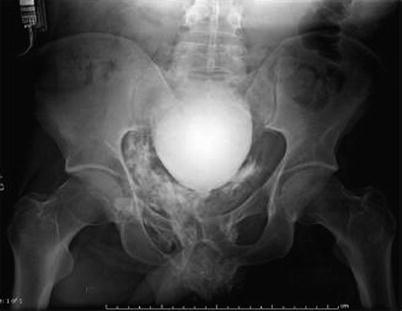

Fig. 20.3

Intraoperative excretory pyelography with complete proximal ureteral disruption. This intraoperative investigation of the urinary tract was made after completion of the damage control procedure

Pyelography can be performed either as an excretory pyelography or as a retrograde pyelography. With a sensitivity of approximately 30 %, excretory pyelography is relatively insensitive for the diagnosis of renal injuries and urine leaks. However, in initially unstable patients, excretory pyelography may be useful to investigate the urinary tract intraoperatively after completion of the damage control procedure (Fig. 20.3). In the presence of hematuria or a suspicious penetrating injury tract, a “single shot” excretory IVP is performed intraoperatively. Ten minutes after intravenous injection of 2 cc/kg of contrast, a single abdominal plain film is taken. This investigation has been shown to obviate renal and ureteral exploration in 32 %.